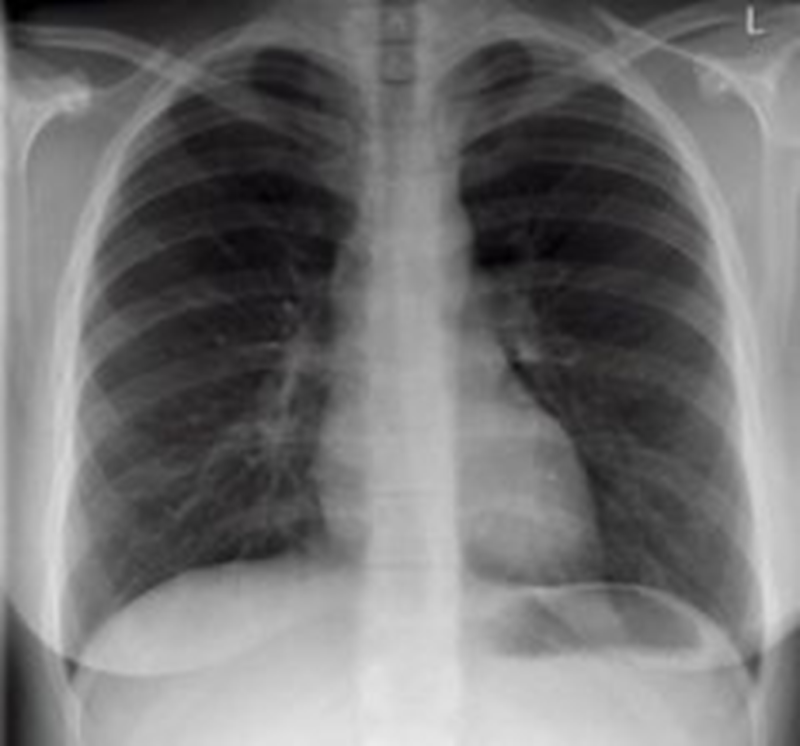

РОЗПІЗНАЙТЕ ОРГАНИ У ФРОНТАЛЬНІЙ ПЛОЩИНІ.

ПІСЛЯ АВТОМОБІЛЬНОЇ АВАРІЇ НА РЕНТГЕНОГРАМІ ВИЯВЛЕНО ПЕРЕЛОМ КІСТКИ В ДІЛЯНЦІ ХІРУРГІЧНОЇ ШИЙКИ. ЯКА КІСТКА МАЄ ТАКУ ШИЙКУ?

варіанти відповідей

Запитання 18

РОЗПІЗНАЙТЕ НА РЕНТГЕНОГРАМІ СУГЛОБ, ЩО МАЄ МІЛКУ СУГЛОБОВУ ЗАПАДИНУ І СКРІПЛЕНИЙ ПЕРЕВАЖНО М'ЯЗАМИ, ТОМУ ТУТ ВІДНОСНО ЧАСТО БУВАЮТЬ ВИВИХИ.

Запитання 20

НА ЯКИЙ СУГЛОБ ВКАЗУЄ СТРІЛКА НА РЕНТГЕНОГРАМІ? КІСТКИ ЯКОГО ВІДДІЛУ СКЕЛЕТУ ВІН З'ЄДНУЄ?

ГРУДНИННО-КЛЮЧИЧНИЙ С.

ПЛЕЧОВИЙ С.

НАДПЛЕЧОВО-КЛЮЧИЧНИЙ С.

АКРОМІАЛЬНО-КЛЮЧИЧНИЙ С.

КІСТКИ ВЕРХНЬОЇ КІНЦІВКИ

КІСТКИ ТУЛУБА І ВЕРХНЬОЇ КІНЦІВКИ

Запитання 21

РОЗПІЗНАЙТЕ НА РЕНТГЕНОГРАМІ СУГЛОБ, ЩО СКЛАДАЄТЬСЯ З ТРЬОХ СУГЛОБІВ, ЯКІ МАЮТЬ СПІЛЬНУ КАПСУЛУ.